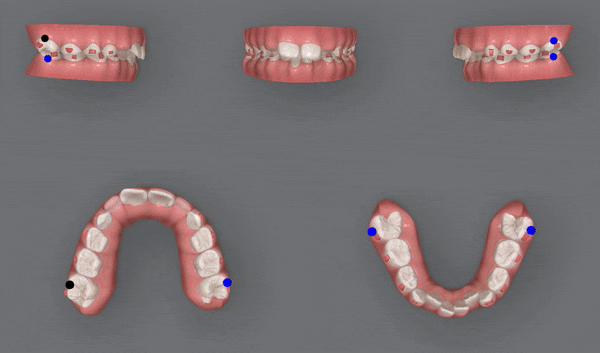

2nd Clincheck (10개)

교정기간 24/1~24/4

두번째 클린체크 는

인비절라인 10개의 장치로 이어서 진행해드렸습니다.

첫번째 클린체크에 추가적으로 어태치먼트를 부착하여

치아배열을 개선시켜 주었습니다.

어태치먼트란?

치아의 회전이나, 이동, 높이, 각도 등을 조절할 수 있는 장치로

레진을 치아에 부착해서

치아의 이동을 원하는 위치로 올바르게 배열시켜 주는

인비절라인에서 없어서는 안 될 필수 요소입니다.